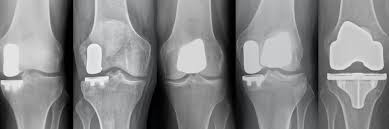

다만, 부상으로 인한 무릎통증은 병원을 찾아 X-레이 또는 초음파로 그 상태를 확실하게 진단받는 것이 중요합니다.